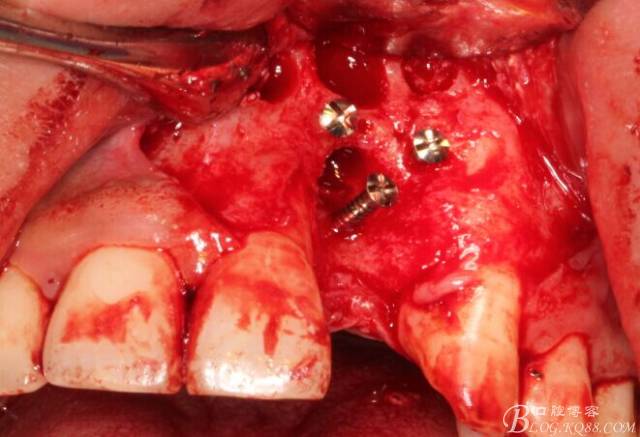

于是我果斷告知患者,手術(shù)失敗了,不能拖延,如不及時處理,炎癥繼續(xù)發(fā)展會很快波及鄰牙牙槽骨?;颊呓邮芪业慕ㄗh。切開翻瓣,骨粉及生物膜消失了,骨吸收嚴(yán)重,幸運的是,因為處理及時,鄰牙骨支持依然存在。

徹底掻刮。